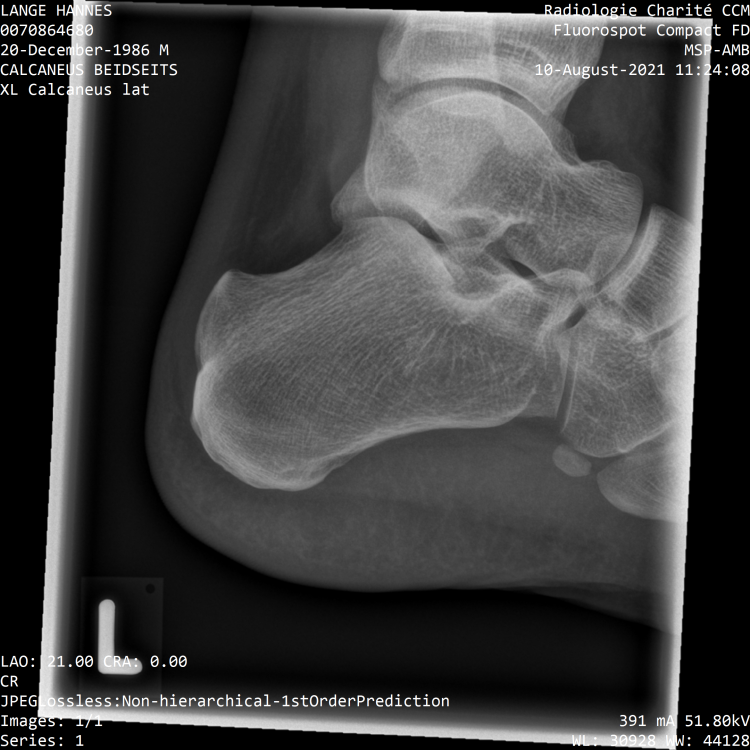

Meine nochmal zum Vergleich Wie war das noch, wurde bei dir hinten operiert und der Knochen abgetragen? Ich habe ja diese Haifischflosse.- 161 Antworten

Stimmt in deinem MRT kann man auch die dorsalen Sporne erkennen. Das zeigt ja eindeutig das bei dir auch die rückseitige Kette verkürzt ist und sie gedehnt werden muss. Die plantaren Sporne sind dann wohl noch nicht verknöchert, dann würde ich hier auch viel die plantare Sehne dehnen und jeden Tag mehrmals den Fuß auf Golfball und Flummies ausrollen, vorallem auch im Bereich der noch nicht verknöcherten Sporne, so kannst du den Prozess der Verknöcherung vielleicht aufhalten. Ich glaube der Körper versucht mit den Spornen der verkürzen Sehne entgegenzukommen. Je kürzer die Sehne desto länger muss der Sporn sein. Je höher die Zugkräfte des schneller entstehen die Sporne. kannst du die Röngtenaufnahmen hochladen? Ich dehne mittlerweile 1. vor dem Aufstehen 2. ca. 2-3h später 3. nach der Arbeit ca. 19 / 20Uhr 4. Kurz vor dem ins Bett gehen Das hat sich bisher am effektivsten gezeigt. Evtl. auch nochmal ein zwischen dem 3. und 4. mal dehnen. Die ersten beiden Dehnungen sind meiner Meinung nach die Wichtigsten da mit der 1. die Verkürzung aus der Nacht reduziert wird und mit der 2. kommt man wieder auf den Zustand vom Vortag. Die ersten beiden male dehne ich auf zwei verschiedene Varianten. Einmal mit dem Spanngurt über dem Ballen für eine gute Dehnung von Wade und Oberschenkel und dann den Spanngurt über die Ferse für eine gute Dehnung des Oberschenkels. Bei mir geht es immernoch nur sehr langsam voran. Es schwankt auch stark. Ich bin mal optimistisch und sage das ich es dieses Jahr zumindest soweit habe das ich normal meinen Alltag bestreiten kann. Am Montag probiere ich mal die Lasertherapie. Ich glaube aber nicht an einen durchschlagenden Erfolg.- 161 Antworten